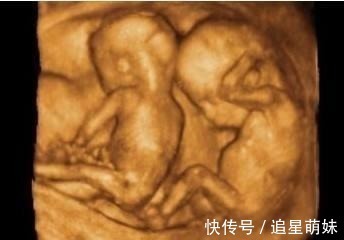

很快的手术就开始了,由于是三胞胎,护士和医生在整个手术的过程中显得十分的小心翼翼,深怕自己一个不小心哪个步骤出错了就会伤害到孕妇和孩子。大约十分钟之后,老大平安降生,接着,老二,老三也相继出生,可当医生把第三个孩子抱出来的时候,却发现圆圆怀的不止三个孩子,还有一个孩子蜷缩在孕妇的体内,这个孩子相比其他三个孩子来说更加的瘦小,这四个孩子还都清一色的都是男孩子。产房外等着的家人听着母子平安都纷纷送了一口气。